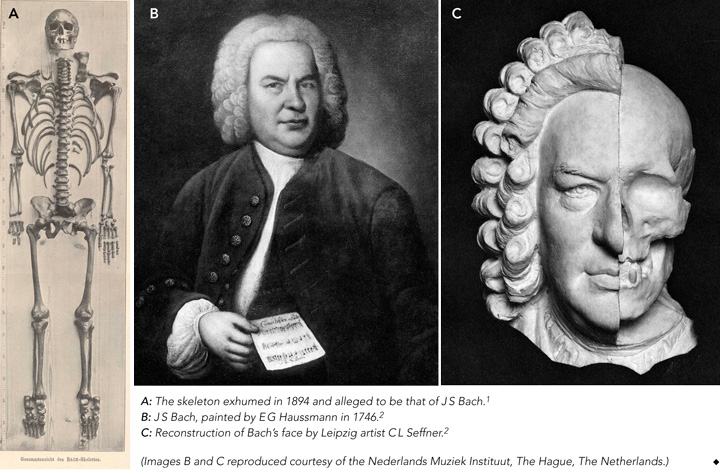

There has been much conjecture about the authenticity of this skeleton and it has been examined several times to establish its identity. In 1894, anatomist Wilhelm His reconstructed the face1,2 and, with remarkable foresight, took into account the possibility of future research, discussing the possibility of “our descendants in later centuries wanting to examine the skull”.2 In 1949, surgeon Wolfgang Rosenthal noted abnormalities of the skeleton that corresponded with those he saw in radiographs of living church organists, leading him to propose a musculoskeletal condition, Organistenkrankheit (“organist’s disease”).3

Several years after Bach’s burial in July 1750, the exact location of his grave was unclear.1-6 Based on oral tradition, it was in the graveyard surrounding St Johanniskirche in Leipzig, “six paces away from the south portal”.4 This oral tradition apparently originated in 1894 from a 75-year-old man, who in turn was informed about the location 60 years earlier by a 90-year-old gardener employed at the graveyard.4 Composer Robert Schumann attempted unsuccessfully to find Bach’s grave (in 1836), as did Leipzig historians Carl Gretschel and Heinrich Heinlein, who both published books on the history of the graveyard (in 1836 and 1844, respectively).4

Before the 1894 exhumation, Leipzig’s director of archives Gustav Wustmann determined that Bach was buried in one of the so-called superficial graves, whose location was not registered.4 Compounding the difficulty, in the year of Bach’s death, no graves were marked with a memorial stone. However, unusually for the time, Bach was buried in an oaken coffin (of the 1400 people who died in Leipzig in 1750, only 12 were buried in such a coffin).4

Thus, when — according to local oral tradition — an oaken coffin containing the skeleton of a man aged about 65 years was found at a depth of 2.37 m in the specified area of the graveyard on 22 October 1894, it was, after the research by His, believed likely to be the remains of Bach.2,5

In 1895, Wilhelm His published a thorough examination of the remains (Box 1, A), including 22 pages describing and illustrating the skull.1 He particularly emphasised his examination of the temporal bone to detect any extraordinary developmental features related to the sense of hearing, which he believed would indicate musical talent. His findings included strong development of the promontory overlying the first coil of the cochlea of the petrous bone,1 which he supposed to indicate a well developed hearing organ. However, we believe it was far more likely to be related to overall skull size.

His also described examining the facial soft tissue of 37 bodies in relation to the underlying skull, as a basis for reconstructing a replica of the face,1 and correlated this with paintings of Bach (Box 1, B). Using this information, Leipzig artist Carl L Seffner superimposed a reconstruction of the face on a replica of the skull (Box 1, C). This reconstruction showed a face that was logically compatible with those in portraits of Bach. His picture was again superimposed on the skull many years later using computer techniques, with the claim that the portrait fitted the skull.7

The facial reconstruction, together with the site of the grave, nature of the coffin and estimated age of the body at death led His to conclude that the exhumed skeleton was most likely that of Bach.2

Based on the available evidence, we believe it is unlikely that the the skeleton in question is that of Bach. The site of Bach’s grave was based on a doubtful oral tradition, and the value of the coffin being made of oak seems overestimated. Wilhelm His hoped his examination would find indicators of an extraordinarily developed musical talent, although a direct relationship between a highly developed peripheral sense of hearing and musical virtuosity has not been proven. A famous counterexample is Ludwig van Beethoven, who had hearing problems for half his life and wrote many compositions while completely deaf.12 Furthermore, the method His used to reconstruct Bach’s face was based on the assumption of a relationship between the skull and overlying soft tissue, which is disputed.13-15

A skeleton alleged to be that of Johann Sebastian Bach (1685–1750) was exhumed from a graveyard in Leipzig, Germany, in 1894, but its authenticity is not established.

In 1895, anatomist Wilhelm His concluded from his examination of the skeleton and reconstruction of the face that it most likely belonged to Bach.

However, our critical assessment of the remains analysis raises doubts: the localisation of the grave was dubious, and the methods used by His to reconstruct the face are controversial.

We believe it is unlikely that the skeleton is that of Bach; techniques such as DNA analysis might help resolve the question but, to date, church authorities have not approved their use on the skeleton.